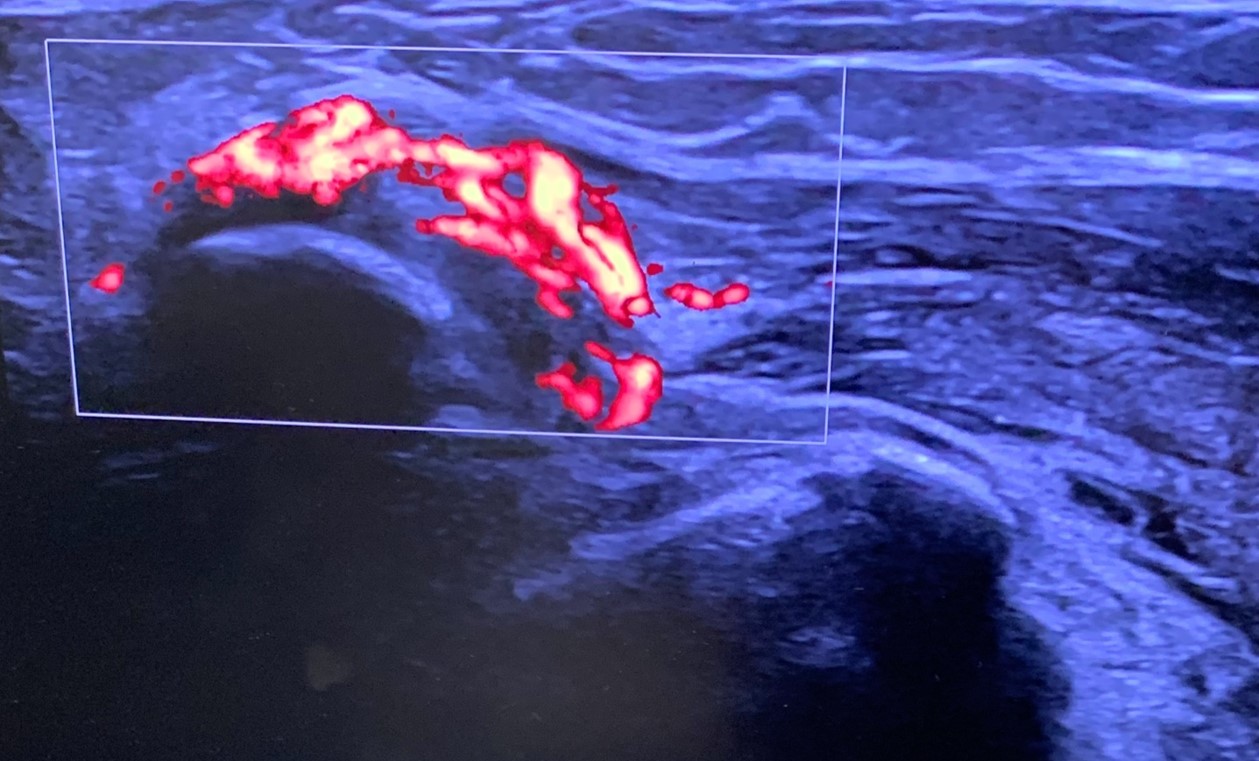

On the dorsum of the foot, ultrasound demonstrated marked cortical irregularity and callus formation around the third metatarsal shaft accounting for the palpable ‘lump’ with surrounding soft tissue swelling (Figure 1). On power Doppler, there was marked peripheral vascularity in the surrounding soft tissues (Figure 2). Incidentally, there was also cortical irregularity and callus formation around the second metatarsal shaft although the patient was not particularly tender here whilst scanning (Figure 3). The cortical irregularity in the second metatarsal shaft was minimal when compared to the third metatarsal and there was no neovascularisation on power Doppler indicating this was an older/mature injury.